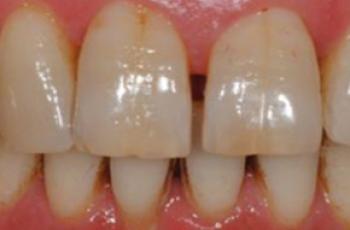

Tratamiento no quirúrgico de la periimplantitis. A propósito de un caso... Cirugía periodontal y periimplantaria | UIC Tratamiento no quirúrgico de la periimplantitis. A propósito de un caso... Se presenta el caso de una paciente de 58 años de edad, sin antecedentes médicos de interés y no fumadora. El motivo... Etiología, diagnóstico y tratamiento de la periimplantitis: Caso... Tto. Periimplantario | UV Etiología, diagnóstico y tratamiento de la periimplantitis: Caso... Presentamos nuevo caso clínico realizado por los doctores Manuel Rodríguez Aranda, Francisco... Efectividad del Tratamiento en Periodontitis Agresiva Tto. Periodontal | UIC Efectividad del Tratamiento en Periodontitis Agresiva El mantenimiento de la dentición natural en estado de salud ha sido un objetivo importante en... Injerto gingival libre alrededor de implantes dentales. A propósito de un... Cirugía periodontal y periimplantaria | UIC Injerto gingival libre alrededor de implantes dentales. A propósito de un... La cirugía mucogingival reconstructiva alrededor de implantes corrige los defectos de la... Terapia mucogingival en implantes: corrección de las secuelas mucosas de... Cirugía periodontal y periimplantaria | UV Terapia mucogingival en implantes: corrección de las secuelas mucosas de... El caso que se presenta a continuación muestra una resolución impecable de un defecto mucogingival... Importancia del mantenimiento en la evolución de un paciente con... Mantenimiento | UV Importancia del mantenimiento en la evolución de un paciente con... La periodontitis agresiva se define como una enfermedad de rápida progresión en la destrucción... Tratamiento de Recesiones Gingivales Clase III de Miller mediante técnica... Cirugía periodontal y periimplantaria | UIC Tratamiento de Recesiones Gingivales Clase III de Miller mediante técnica... El caso clínico que presentamos a continuación es el de una paciente que acude a la consulta... Tratamiento de un paciente con periodontitis crónica moderada generalizada Tto. Periodontal | UIC Tratamiento de un paciente con periodontitis crónica moderada generalizada El caso clínico que se presenta a continuación, muestra el tratamiento de una paciente...